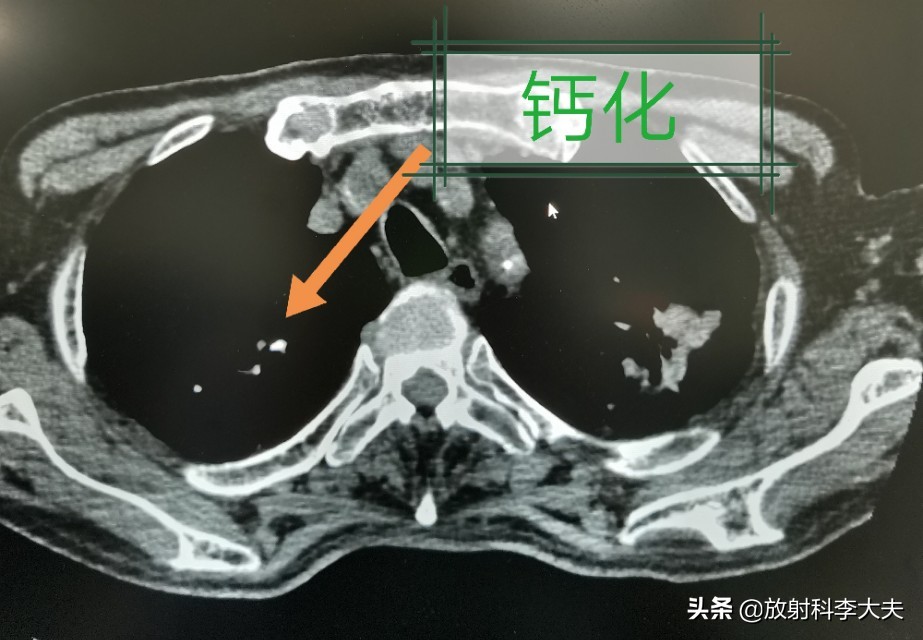

双肺多发的病灶,有的已经钙化,陈旧的结核灶。但是,左肺上叶一个哑铃形状的病变,引起重视。